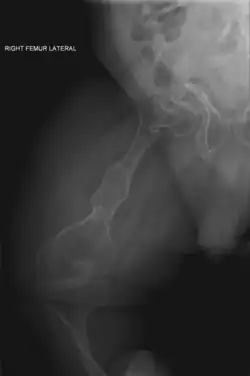

| II | Enfermedad de Vrolik, autosómica recesiva. Se caracteriza por fragilidad ósea extraordinaria, culmina en la muerte en el periodo perinatal o comienzos de la lactancia, huesos largos muy fragmentados (fémur en acordeón), prominencia de hueso parietal y temporal con occipucio colgante y osificación de cráneo retrasada extraordinariamente. |

_of_right_femur.png)